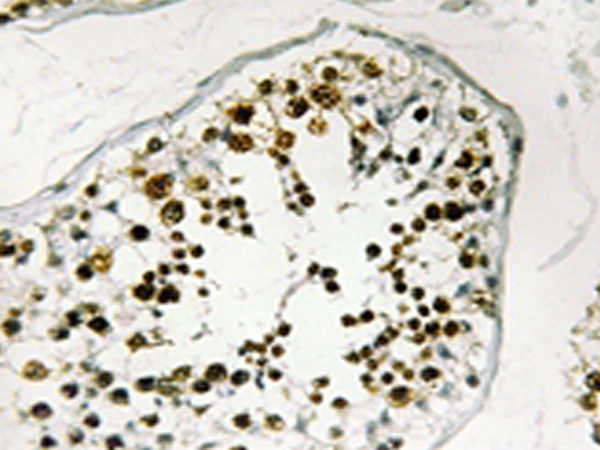

IHC positive control: |

Human testis tissue |

IHC Recommend dilution: |

50-100 |